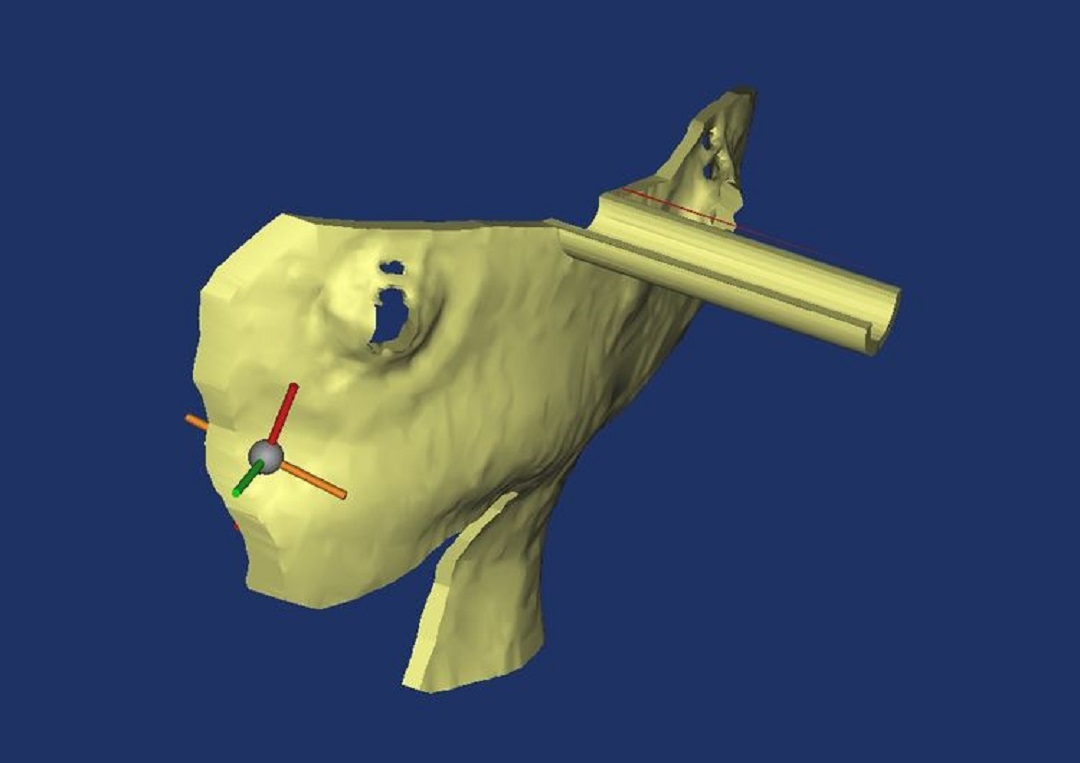

首先采集患者的頭顱螺旋CT原始dicom數(shù)據(jù),將CT數(shù)據(jù)導(dǎo)入計算機(jī),運(yùn)用比利時醫(yī)療三維軟件,運(yùn)用3D重建頭顱面具模型,進(jìn)行血腫3D重建,在三維圖像上設(shè)計穿刺通道,調(diào)整通道在血腫的位置、通道與面具的交叉點,即為穿刺點位,將畫出的部分面具轉(zhuǎn)換成打印機(jī)能識別的gcode代碼,輸入3D 打印機(jī)打印,即為應(yīng)用于手術(shù)中的導(dǎo)航導(dǎo)板(如下圖):

穿刺路徑

導(dǎo)板與血腫

面部導(dǎo)板位置

待打印的導(dǎo)板模型數(shù)據(jù)